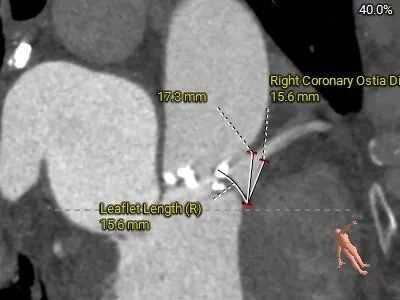

左冠19.4,右冠25.8,综合分析冠脉阻挡风险适中

•左、右冠高度可,切线位测量,左窦瓣叶略长于左冠开口下缘;左主干分叉附近可见钙化分布,